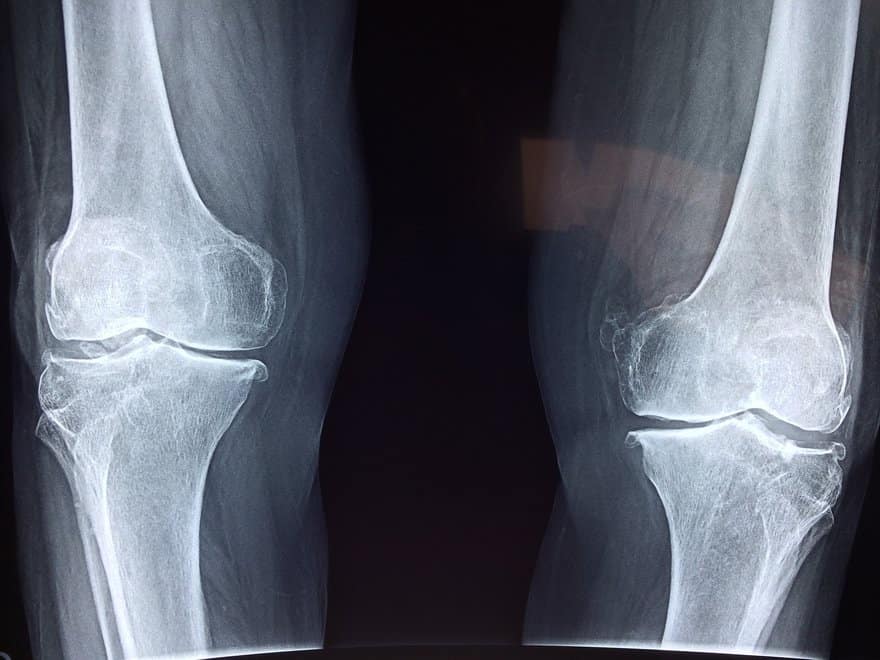

Augmented Reality (AR) Assisted Double Total Knee Replacements Augmented Reality Knee Replacement Augmented reality (ar) technologies aimed to introduce virtual elements into the user’s environment [e.g., superimposition of the. The augmented reality knee replacement platform—nextar™ tka—received clearance from the fda in 2020. Nextar knee is a personalized, proprietary, and sustainable augmented reality surgical application for total knee replacement. The process begins when surgeons take a preoperative ct scan of the patient’s knee. Augmented Reality Knee Replacement.